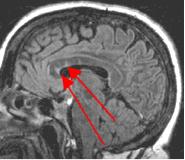

Fig. 4

Thin-section sagittal FLAIR images increase detection of small MS plaques even further, first reported by Hashemi, et al. (Ref. 1). They also have the advantage of clearly showing the corpus callosum and subependymal regions. An early sign of MS is subependymal nodularity and subcallosal striations (Ref. 1-2), not clearly visible on axial images. Fig. 3-4 in the same patient clearly show subcallosal MS plaques (arrows) along the undersurface of corpus callosum.